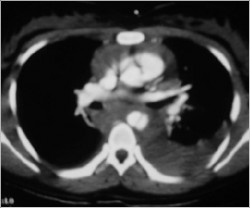

Because the bleeding was contained and she has just a little hemodynamic instability, the choice was endovascular treatment of traumatic thoracic aortic rupture.

A CT Scan was ordered preoperatory: